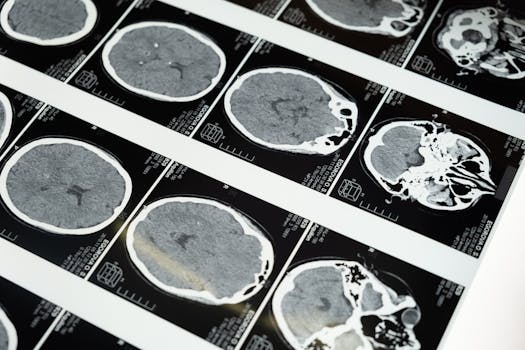

When a TBI Diagnosis Demands More Than Just Medical Care: Finding Your Legal Champion

Navigating TBI claims? Discover when a traumatic brain injury lawyer is your essential ally for justice and maximum compensation.